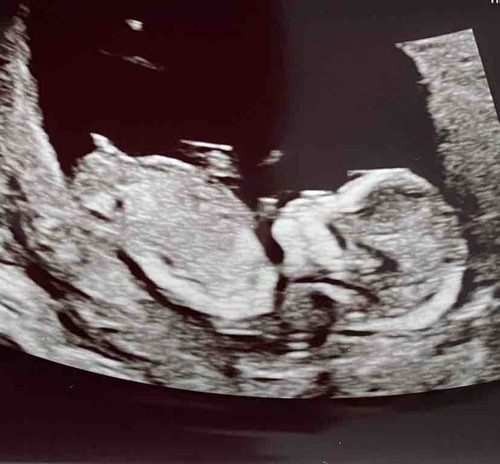

13 weken echo, wat denken jullie? Ik ben heel nieuwsgierig

Jongen